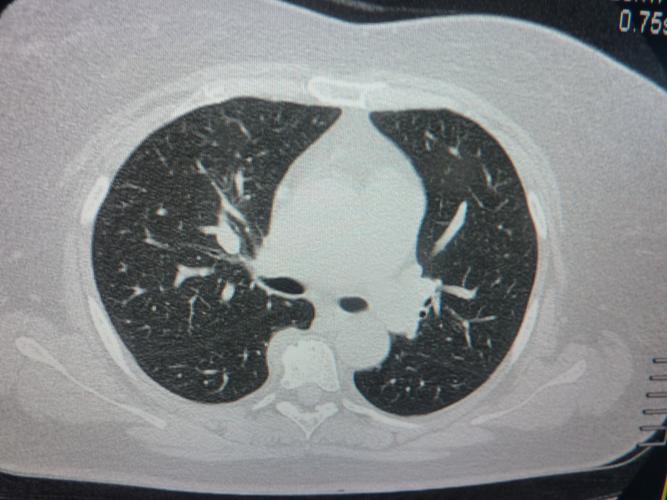

正常肺门图片CT

正常肺门图片CT,正常肺ct片图片图解

肺部ct,有没有看得懂的,帮忙看一下,我爸爸的,我很担心.谢谢.

ct52812右肺门旁是血管影

胸部x射线 ct增强片 帮帮忙看一下 是肺癌吗?

外院 肺ct 右肺门浓密及右肺下叶高密度影,左肺上叶支气管扩张,右侧

2009年2月17日复查ct见左肺门病灶明显缩小甚至消失.